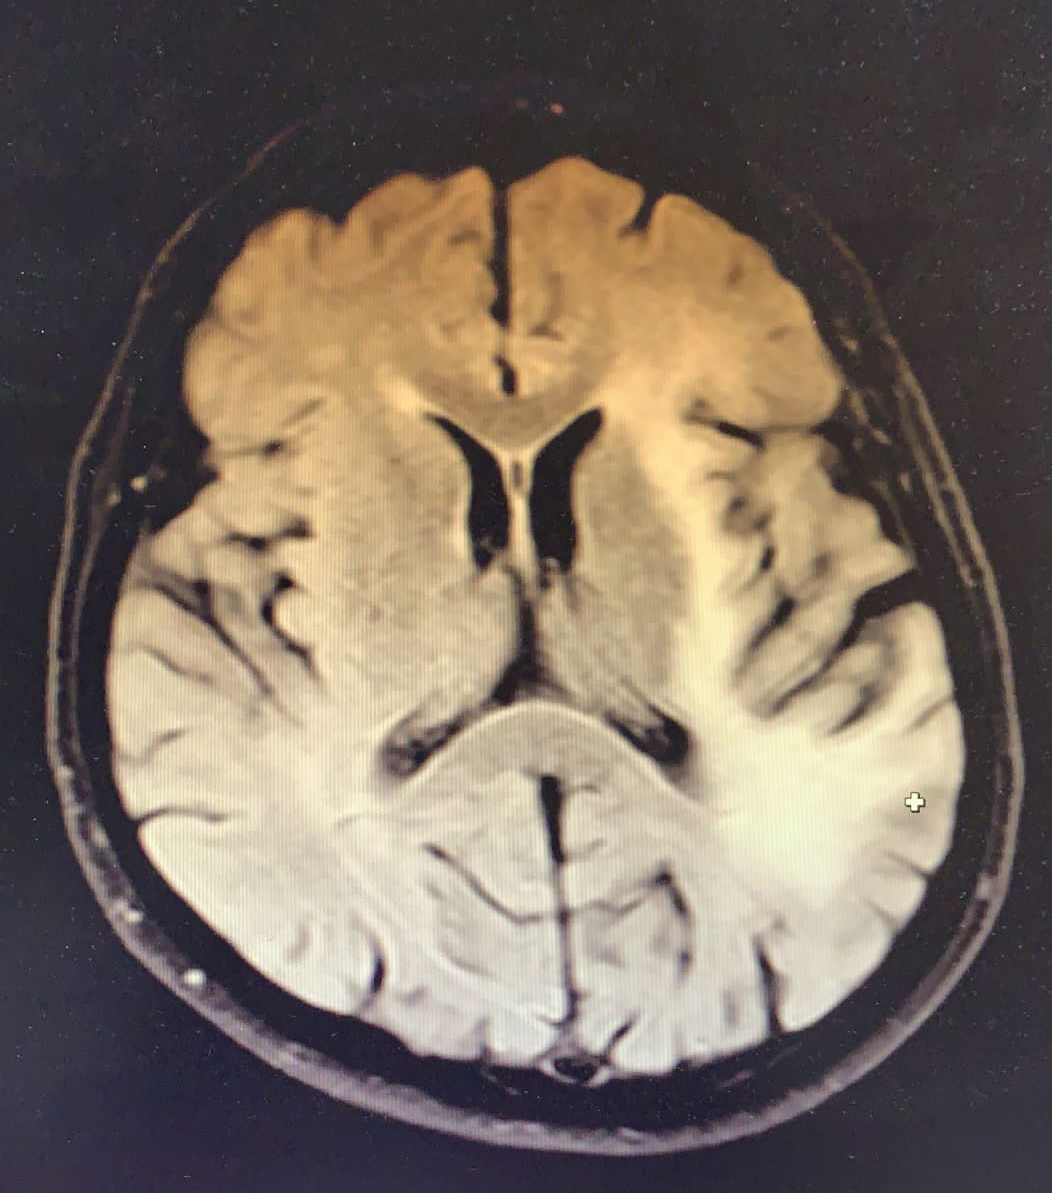

Tedavinin ikinci ayında hasta kliniğimize yaklaşık iki haftadır olan konuşma bozukluğu yakınması ile başvurdu. Fizik muayende genel durumu iyi, şuuru açık, konuşması afazikti. Basit ve tekli emirleri yerine getirebiliyordu. GKS 15 olan hastada sağ kol ve bacakta kas gücü 4/5 idi, duyu defisiti saptanmadı. Yapılan kontrastlı kranial görüntüleme bir önceki kranial MRG tetkiki ile kıyaslandığında eski tetkikte lezyonun insular korteksle sınırlı olduğu güncel incelemede ise kısa sürede belirgin progresif değişiklikler geliştiği şeklinde raporlandı (Resim 2).